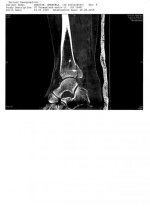

Ich muss ständig der Bein hochhalten .Ich habe bis jetzt 4 KG hinter mir . Dazu muss ich noch was schreiben . 2 Tagen nach OP erfolgte ein MRT , da ist festgestellt worden , OP Arzt hat ein Splitter "nicht gesehen" . Ich war nicht bereit von ein neuen Angriff , diesmal durch Achillesferse um der Splitter zu entfernen . Weißt jemand die Heilungsdauer ? Was kann ich tun ?